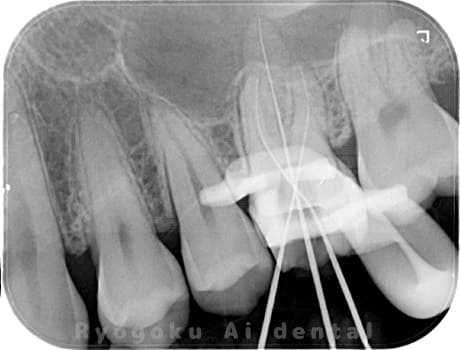

Case02

-

- 原因

- 慢性根尖性歯周炎

- 治療期間

- 3ヶ月

- 治療内容

- マイクロエンド

- 治療費用

- 121,000円

噛むと痛みが出る、とのことで来院した患者様です。他院での根管治療を終えてましたが、根尖病変を認めるため、マイクロエンドを行いました。